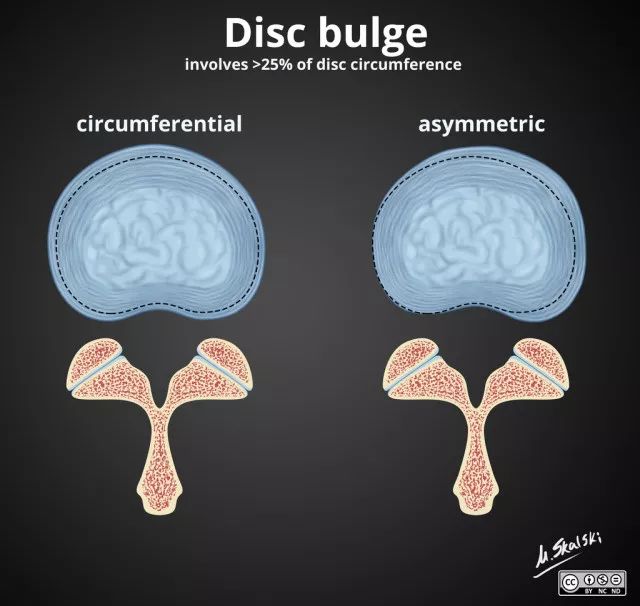

1. 椎间盘膨出(Disc bulge)

纤维环松弛但完整,髓核皱缩,表现为纤维环均匀超出椎体终板边缘。

图 3 椎间盘膨出的影像学定义为突出部分>椎间盘边缘的25%,或者突出的两边与髓核的中心的夹角>90°